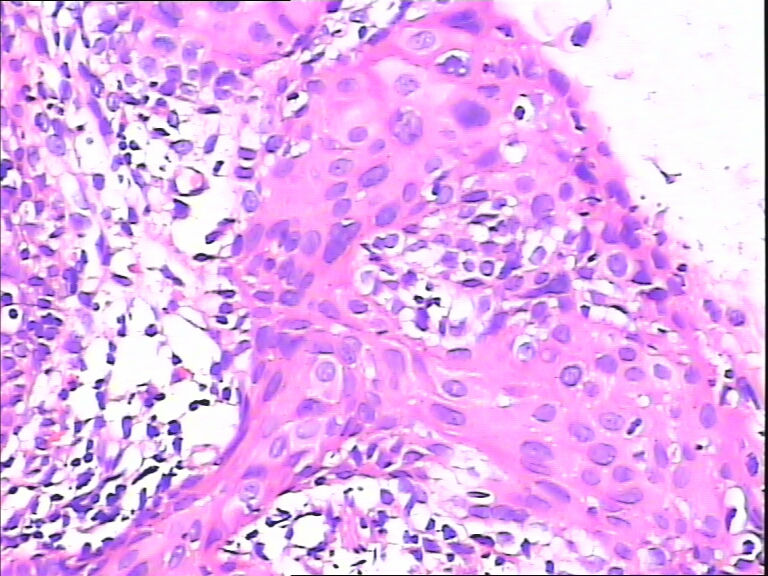

45y,触血,宫颈多点活检。